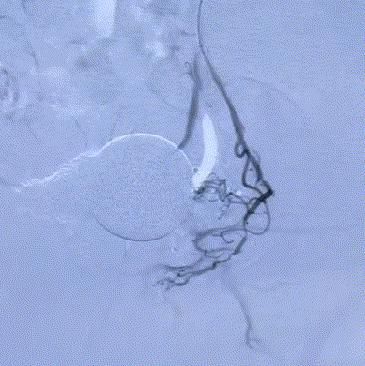

△術前,可見前列腺供血豐富。

△術後,前列腺供血動脈被成功阻斷。